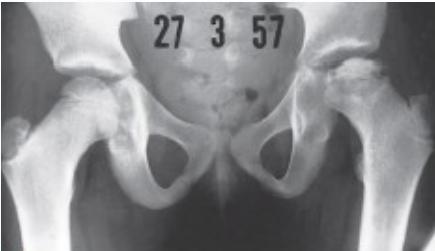

Radiographic Stages:

-

Initial/ Bone Death Stage - May initially appear normal on x-ray

- Increased density followed by collapse

Revascularization and Repair Stage - Reduced density and fragmentation on x-ray

Distortion and Remodeling Stage - Distortion, flattening (coxa plana)

- Enlargement (coxa magna) with partial uncoverage

Radiological Progression:

Progression: Sclerosis → Collapse → Fragmentation → Remodeling

Imaging Examples: